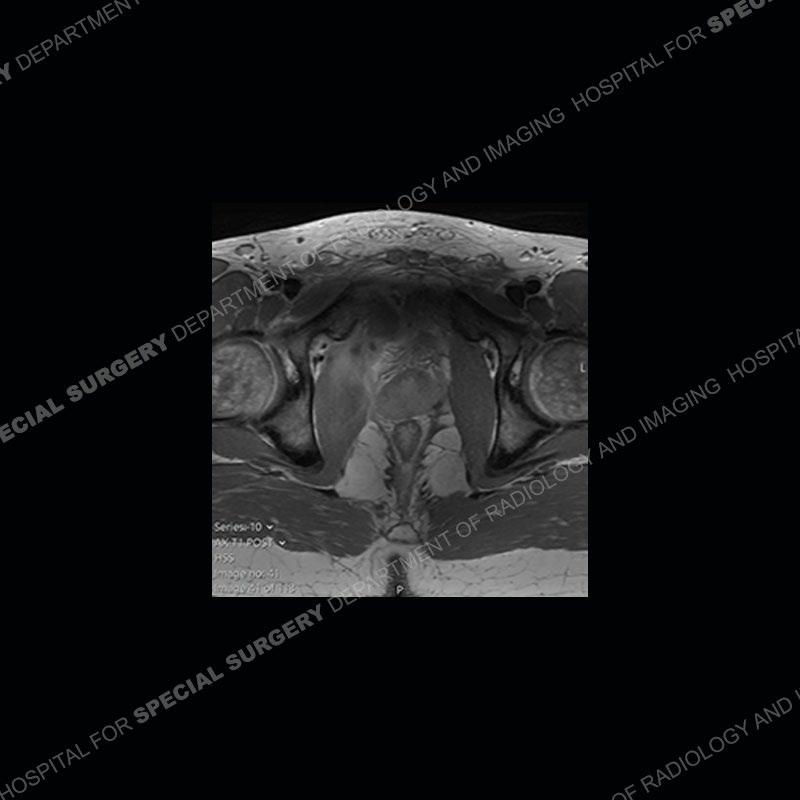

Radiographs did not demonstrate any clear abnormality. The MRI shows markedly abnormal signal of the right superior pubic ramus and abnormal signal/”mass” extending into the adjacent soft tissue. The inferior articular surface of the ramus showed what was thought to be bony destruction. CT examination shows a destructive process of the right superior pubic ramus.

Subsequent MRI in a very short time interval shows markedly increased abnormality of the ramus and increased edema and “mass” of the soft tissue. Post contrast imaging shows multiple, rim enhancing collections of the soft tissue and similar albeit less conspicuous enhancing collection of the ramus.

Diagnosis: Osteomyelitis and Soft Tissue Abscess

The repeat MRI, with the marked degree of increased abnormality of the bone and soft tissue shifted the diagnosis to a high degree towards infection. Even the most aggressive of neoplasms would not have that the degree of change in a 3-day time span. The CT study was shown before the repeat MRI but actually occurred just after the repeat MRI. It helped confirm the destructive process of the ramus and particularly the abnormal architecture along the inferior margin. The patient went on to have a CT guided aspiration of one of the soft tissue collections with 4cc of purulent fluid obtained. A surgical irrigation and debridement of the bone and soft tissue was performed. A PICC line was placed and the patient is currently undergoing IV antibiotic treatment with a possible repeat irrigation and debridement.